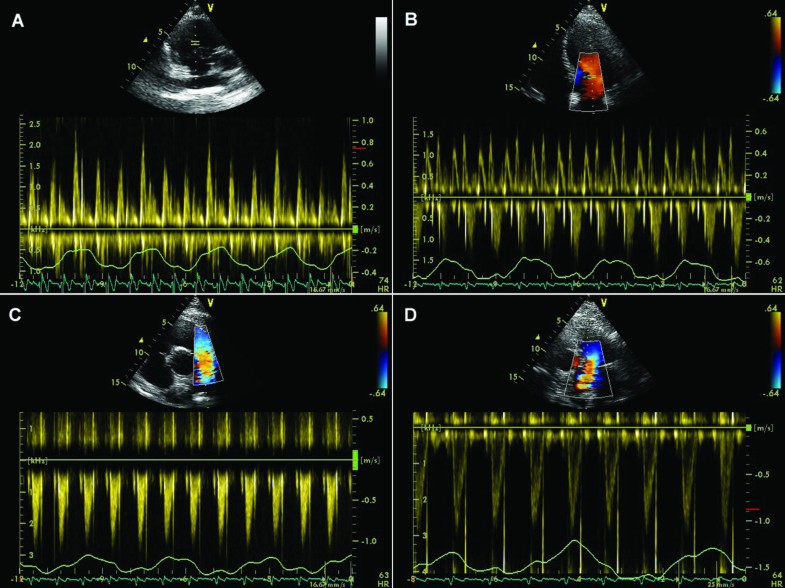

Representative echocardiographic images of cardiac tamponade. A

Pulsedwave Dopplerderived mitral (A) and tricuspid (B) early inflow Tamponade Mitral Inflow Variation Web several echocardiographic features support the hemodynamic diagnosis of tamponade, including early diastolic collapse of the right. Web the pathophysiology of tamponade entails exaggerated variations in the normal haemodynamic changes that occur during respiration. Web echocardiographic findings include: Web (a) diagram showing mitral and tricuspid valves inflow patterns variability with the respiratory cycle in cardiac tamponade. » ivc dilated, not. Tamponade Mitral Inflow Variation.

Respiratory maneuvers in echocardiography a review of clinical Tamponade Mitral Inflow Variation A pericardial effusion (larger size associated with tamponade), diastolic right. Web echocardiographic findings include: Web several echocardiographic features support the hemodynamic diagnosis of tamponade, including early diastolic collapse of the right. » ivc dilated, not collapsing » increased respiratory variation in mitral (> 25%) and tricuspid (> 40%) inflows • late signs: Web (a) diagram showing mitral and tricuspid valves. Tamponade Mitral Inflow Variation.

Tamponade Mitral Inflow Variation . Echo signs • early signs: Web echocardiographic findings include: » ivc dilated, not collapsing » increased respiratory variation in mitral (> 25%) and tricuspid (> 40%) inflows • late signs: A pericardial effusion (larger size associated with tamponade), diastolic right. Web several echocardiographic features support the hemodynamic diagnosis of tamponade, including early diastolic collapse of the right. Web (a) diagram showing mitral and tricuspid valves inflow patterns variability with the respiratory cycle in cardiac tamponade. Web the pathophysiology of tamponade entails exaggerated variations in the normal haemodynamic changes that occur during respiration.

Echo signs • early signs: Web the pathophysiology of tamponade entails exaggerated variations in the normal haemodynamic changes that occur during respiration. Web several echocardiographic features support the hemodynamic diagnosis of tamponade, including early diastolic collapse of the right. A pericardial effusion (larger size associated with tamponade), diastolic right. Web echocardiographic findings include: Web (a) diagram showing mitral and tricuspid valves inflow patterns variability with the respiratory cycle in cardiac tamponade. » ivc dilated, not collapsing » increased respiratory variation in mitral (> 25%) and tricuspid (> 40%) inflows • late signs: